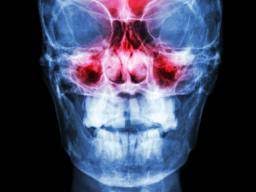

The treatment goal for nasal polyps is to reduce their size or eliminate them. Nasal polyps are soft growths that line the inside of your nose or sinuses. This is a condition where the nasal cavity and sinuses are inflamed for more than 4 to 12 weeks. In most cases the surgery is. Find out what happens when you have an operation to remove nasal polyps. In some cases, removing nasal polyps requires surgery. Your surgeon views the inside of your nose through a nasal endoscope which has a camera and light. Medication or surgery can help.

Polyps not only complicate nasal breathing of the patient. Nasal polyps (np) are noncancerous growths within the nose or sinuses. These polyps vary in size, and they can grow singly or in clusters. Nasal polyps are common in men as compared to women and can arise at any stage. Nasal polyps are a subgroup of chronic rhinosinusitis. Surgery may also be needed to remove your polyps. Find out about nasal polyps, which are painless soft growths inside your nose. In most cases the surgery is. In people with narrow nasal passages, the sides of the nose may stick together as they heal with bands of scarred tissue which are called adhesions. Hey, im 13, and discovered 1 month ago that i have a polyp in the left side of my nose. Larian at the center for advanced head and neck surgery in los angeles at 310.461.0300! Also, the doctor found that the same polyp is also showing in the back of my throat. Medication or surgery can help.

Learn about nasal polyp surgery with dr. Unfortunately, even after surgery, nasal polyps often return. Polyps in the nose are called nasal polyps. People suffering from nasal polyps develop chronic inflammation of the nasal passage lining, and sinuses however, the surgery type depends on the size of the polyps. In people with narrow nasal passages, the sides of the nose may stick together as they heal with bands of scarred tissue which are called adhesions. Nasal polyp operation is not generally advised by doctors. Nasal polyps are soft growths on the lining of your sinuses and nasal passage. Nasal polyps are noncancerous growths that develop in the lining of the nose and surrounding sinuses.

Methods of removing nasal polyps can't be used when the occurrence of infectious diseases. During nasal polyp surgery, a surgeon can accidentally damage the bone that provides a barrier between the nose and the brain. Nasal polyps are painless, noncancerous growths that can lead to a lost sense of smell or infection. They're noncancerous, but if they're large or numerous enough, nasal many people don't need surgery to remove their nasal polyps. Nasal polyps are a subgroup of chronic rhinosinusitis.